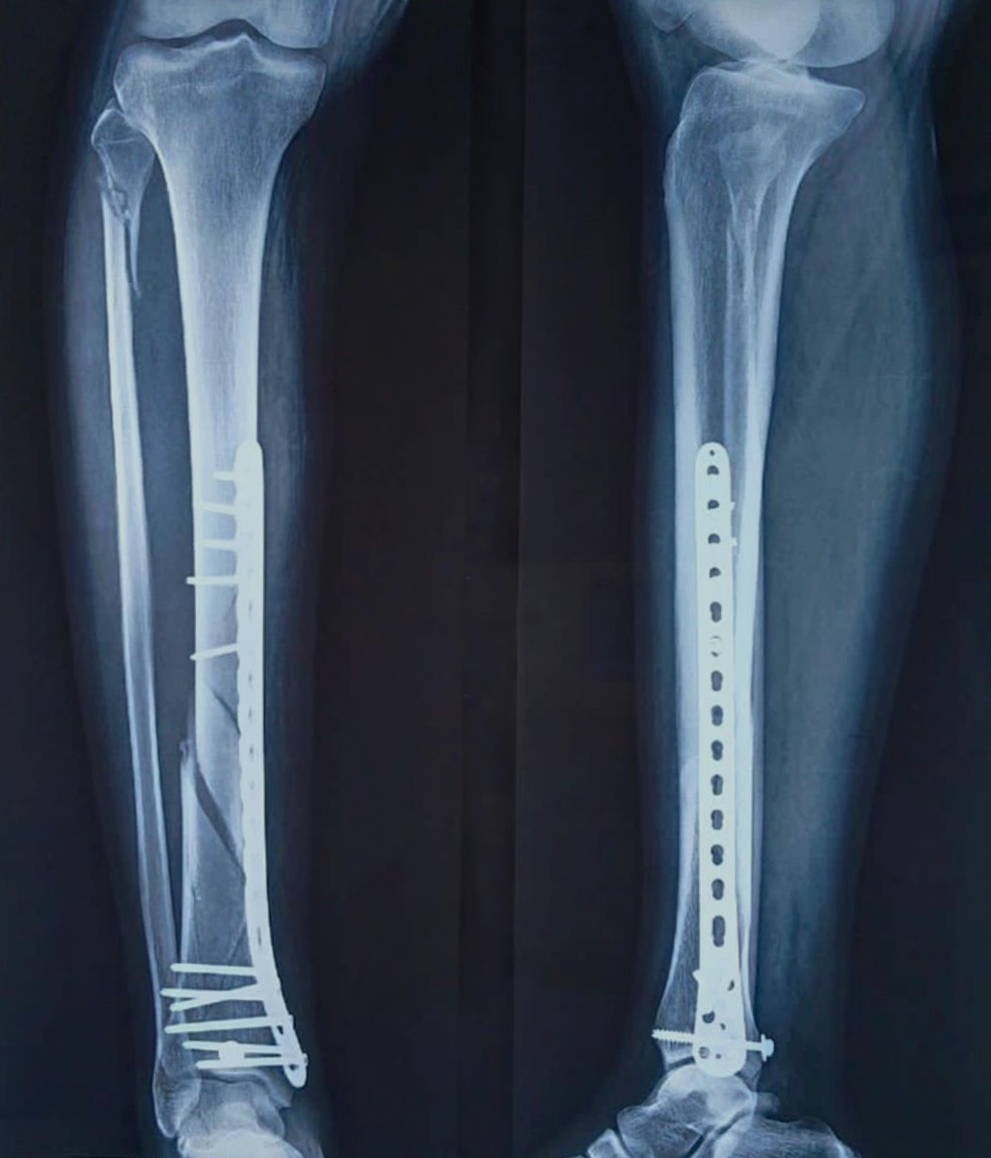

- Fracture Treatment: We specialize in the surgical and non-surgical treatment of

fractures, utilizing advanced techniques to ensure optimal healing and recovery.

- Expertise in Trauma Care: Dr. Zambare is highly skilled in managing complex trauma

cases, including multi-limb injuries and severe fractures. His expertise ensures that patients receive

precise and effective treatment for their injuries.

- Imaging and Diagnostic Services: We offer comprehensive imaging and diagnostic

services, including high-resolution X-rays and orthoscannograms, to accurately diagnose and plan

treatment for orthopaedic conditions.